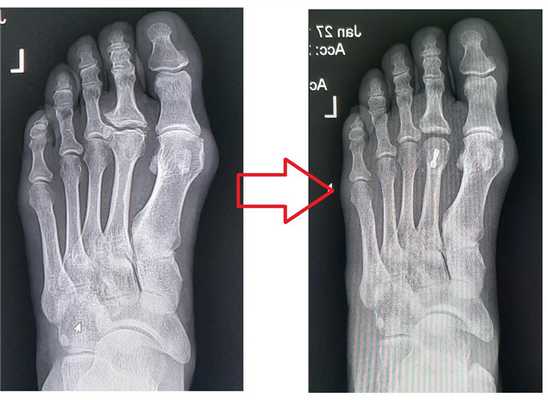

Болезнь Келлера 2 (в отечественной литературе) или болезнь Фрайберга (во всём остальном мире), является следствием развития аваскулярного некроза (или по сути инфаркта) головки 2, реже 3 плюсневой кости стопы. Заболевание проходит ряд последовательных стадий. Первая фаза - дебют заболевания, чаще всего происходит в возрасте 13-18 лет, в 4 раза чаще у девочек. Характеризуется появлением занчительной боли и отёка в проекции поражённой головки плюсневой кости.

Первая фаза болезни келлера 2, или болезни фрайберга.

Ниже приведу клинический пример лечения пациентки с данной патологией.

По классике, начало заболевания у неё произошло в возрасте 15 лет. Несколько месяцев были выраженные боли, она хромала, лечилась у детского ортопеда физиотерапией, была освобождена от физкультуры. Примерно через год боли прошли, и практически не беспокоили её на протяжении 30 лет. Но в течение последних 10 из них она начала отмечать прогрессирующее ограничение амплитуды движений.

На приём она обратилась уже с полным отсутствием тыльного сгибания. При осмотре под кожей был виден огромный экзостоз - который блокировал сгибание пальца.

Принято решение оп роведении хирургического вмешательства - резекции экзостоза, клиновидной остеотомии головки 2 плюсневой кости с фиксацией винтом.